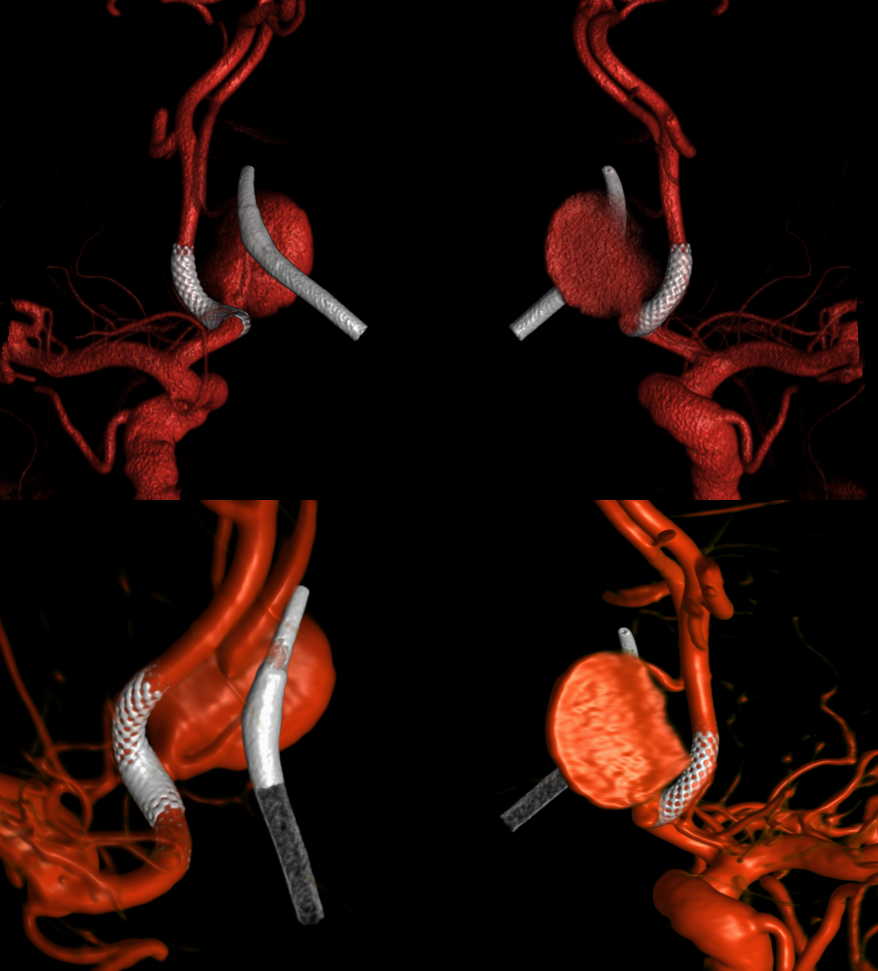

Stereo views of the two craniotomies, with translucent and sonolucent closure

Can we sac the ACOM now? Coil aneurysm and the ACOM? Why not? Can argue for that. We choose H-Flow Diversion. A1-A2 bilaterally. On the right, we have to access the A1-A2 via the PCOM. This is not a job for 27 or 21 catheter. Plan for Silk Vista Baby on right and Pipeline Shield on left

The first SVB is deployed. However, there is a concern. What is it? Look at the measurements of the SVB and the landing zones

The answer is possible endoleak. The distal landing zone may be too short for a nitinol device. The diameter of the proximal SVB is smaller than the expected diameter of the A2 target. Its a critical point. If this is missed, the treatment may fail

The answer is to either balloon it or put in another device. We put in another SBV, now extending it into one of the A2 branches. Yes, one can argue that with working bypass you can just close the A1-A2 junction. Sure. But we did not know this before. And we can always do that later by coiling inside the SVB. Here, we keep options open.

Post SVB 2

Look at the difference in measurements after SBV 2 (top row) and SBV 1 (bottom row). Arrows point to location of the SVB 1 distal landing zone